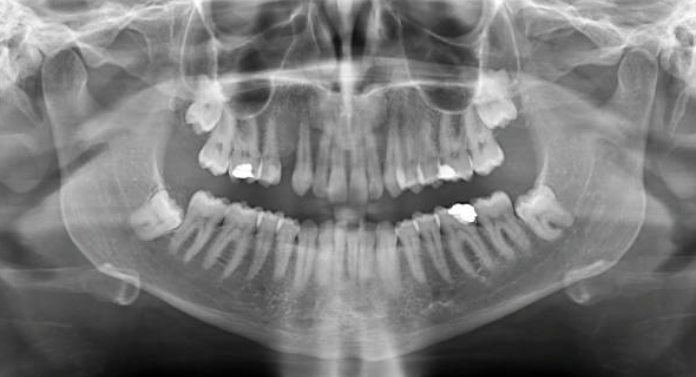

임플란트를 시술할 때 주의해야 할 가장 중요한 점 중 하나는 임플란트 시술 중 턱의 신경을 만지면 신경 마비가 발생할 수 있다는 점을 유의해야 합니다. 신경을 건드리면 얼굴의 일부분이 마비될 수 있으므로, 병원 결정 후 치과에 가서 신중한 진단을 받는 것이 좋습니다. 임플란트 부작용에 대해 자세히 알아보려면 별도의 글을 참조하시기 바랍니다.